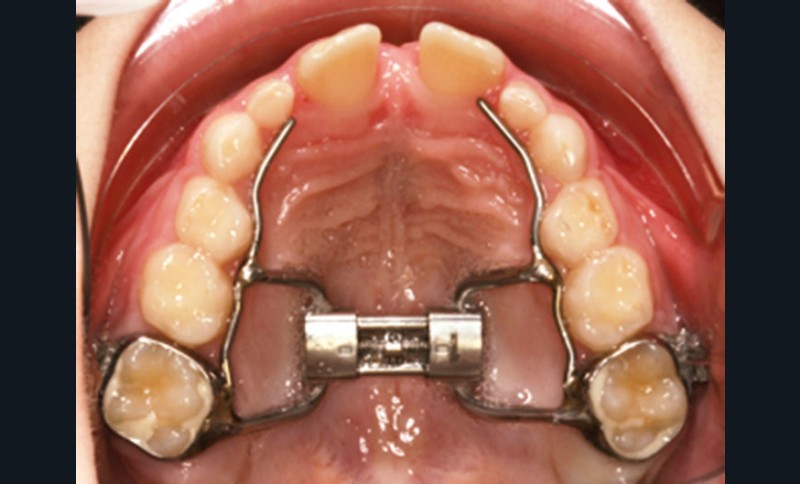

Disjonction intermaxillaire ou distraction maxillaire rapide (DMR)

Dans les années 1960-1970, des orthodontistes, sans connaissance particulière sur le sommeil, avaient déjà rapporté des résultats cliniques positifs lors de parasomnies, en utilisant la distraction maxillaire rapide (DMR) (fig. 3), et démontré l’effet sur les résistances nasales. Les mécanismes par lesquels la DMR entraîne une formation d’os au niveau de la suture palatine, l’élargissant lors de la traction, ont été bien étudiés.

Cette technique s’est montrée très efficace chez le jeune enfant au palais dur étroit et ogival. En trois semaines, avec une expansion en moyenne de 0,25 à 0,50 mm par jour, une nouvelle formation d’os est observée, avec un effet clinique démontré sur la respiration lors du sommeil par PSG. Cette approche a plusieurs avantages, donnant non seulement plus de place au pharynx, mais surtout diminuant considérablement la résistance nasale anormale lors du sommeil. Elle permet aussi de réduire l’impact d’une déviation septale marquée, sans avoir recours à une intervention chirurgicale. En effet, le septum nasal est reconnu comme facteur de croissance crânio-faciale, et une intervention septale chez un enfant prépubertaire, difficile, avec un résultat à long terme souvent médiocre, pourrait affecter la croissance faciale. La DMR peut être réalisée au cours de la croissance de l’enfant jusqu’à ce que l’ossification complète de la suture palatine soit atteinte (entre 14 et 17 ans selon l’enfant). Mais cette intervention orthodontique a des limites : il n’existe pas de cartilage mandibulaire et la distraction du maxillaire est ainsi limitée dans son efficacité.